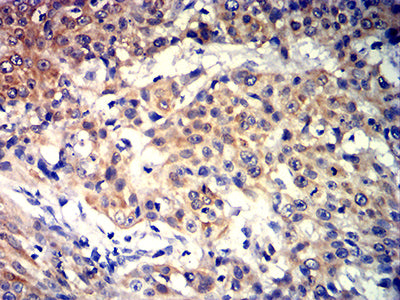

- Immunohistochemical analysis of paraffin-embedded human prostate cancer tissues using KRT10 mouse mAb with DAB staining.

- Immunohistochemical analysis of paraffin-embedded human esophageal cancer tissues using KRT10 mouse mAb with DAB staining.